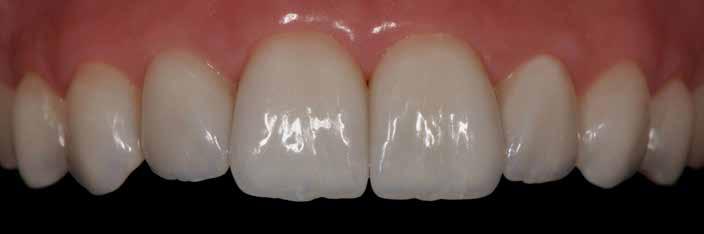

kompozitot. A ragasztó maradványait eltávolítottuk. A végeredmény – a 22 fog tökéletesen, harmonikusan illeszkedik a maradék fogazatba (41. kép)

A páciens, ajánlásunk ellenére, sajnos nem kívánta felújíttatni a két szomszédos koronáját. Ez – tekintetbe véve magas